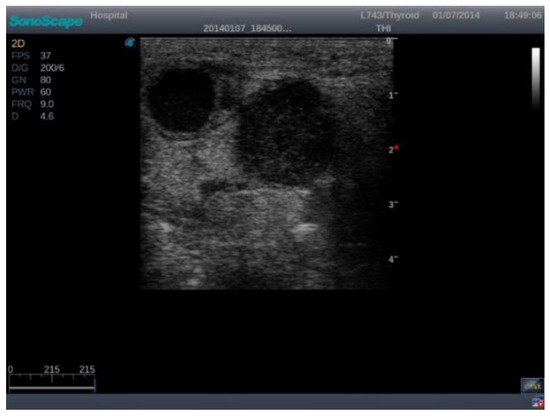

A database consisting of images of 220 patients (8540 B-mode images) was analyzed. The patients selected underwent cervical US imaging via a Sonoscape S2 (2012) Portable US Machine between 2012 and 2023. The database was anonymized by refraining from saving patient information during the investigation. Codes randomly generated by the US machine were used. The images were analyzed by a team consisting of 1 ENT physician, 1 radiology physician, and 1 nuclear medicine resident. According to the inclusion criteria, the patients included in this study had to have at least one suspicious lymph node image, the images had to be clear, and all 3 physicians had to agree on the presence of the lymph node in the selected image. The exclusion criteria consisted of blurred images, the presence of annotation (such as dimensional axes), and Doppler signal or elastography windows. Although these features are important, we chose to exclude the Doppler and elastography windows due to the limited number of cases containing both, as their inclusion would have significantly reduced the dataset and led to a lack of normal images. After applying the criteria, a total of 53 patients (166 images) were chosen. From the 166 images obtained, 150 were selected to augment the data for training and validation, while 16 were kept original for testing. The remaining 150 training images were then cut using the original bounding boxes to obtain positive and negative images (with lymph nodes and without lymph nodes) with dimensions of 100 × 100 in order to train the neural network. This process led to a total of 1732 small, 100 × 100 images either containing a full-size lymph node or a background of the main image.

The images were exported from the device used in .jpg format (Figure 1) directly from the US machine and processed by cropping them and resizing them to 469 × 469 pixels (Figure 2).

Figure 1. Raw US machine image of a malignant lymph node.